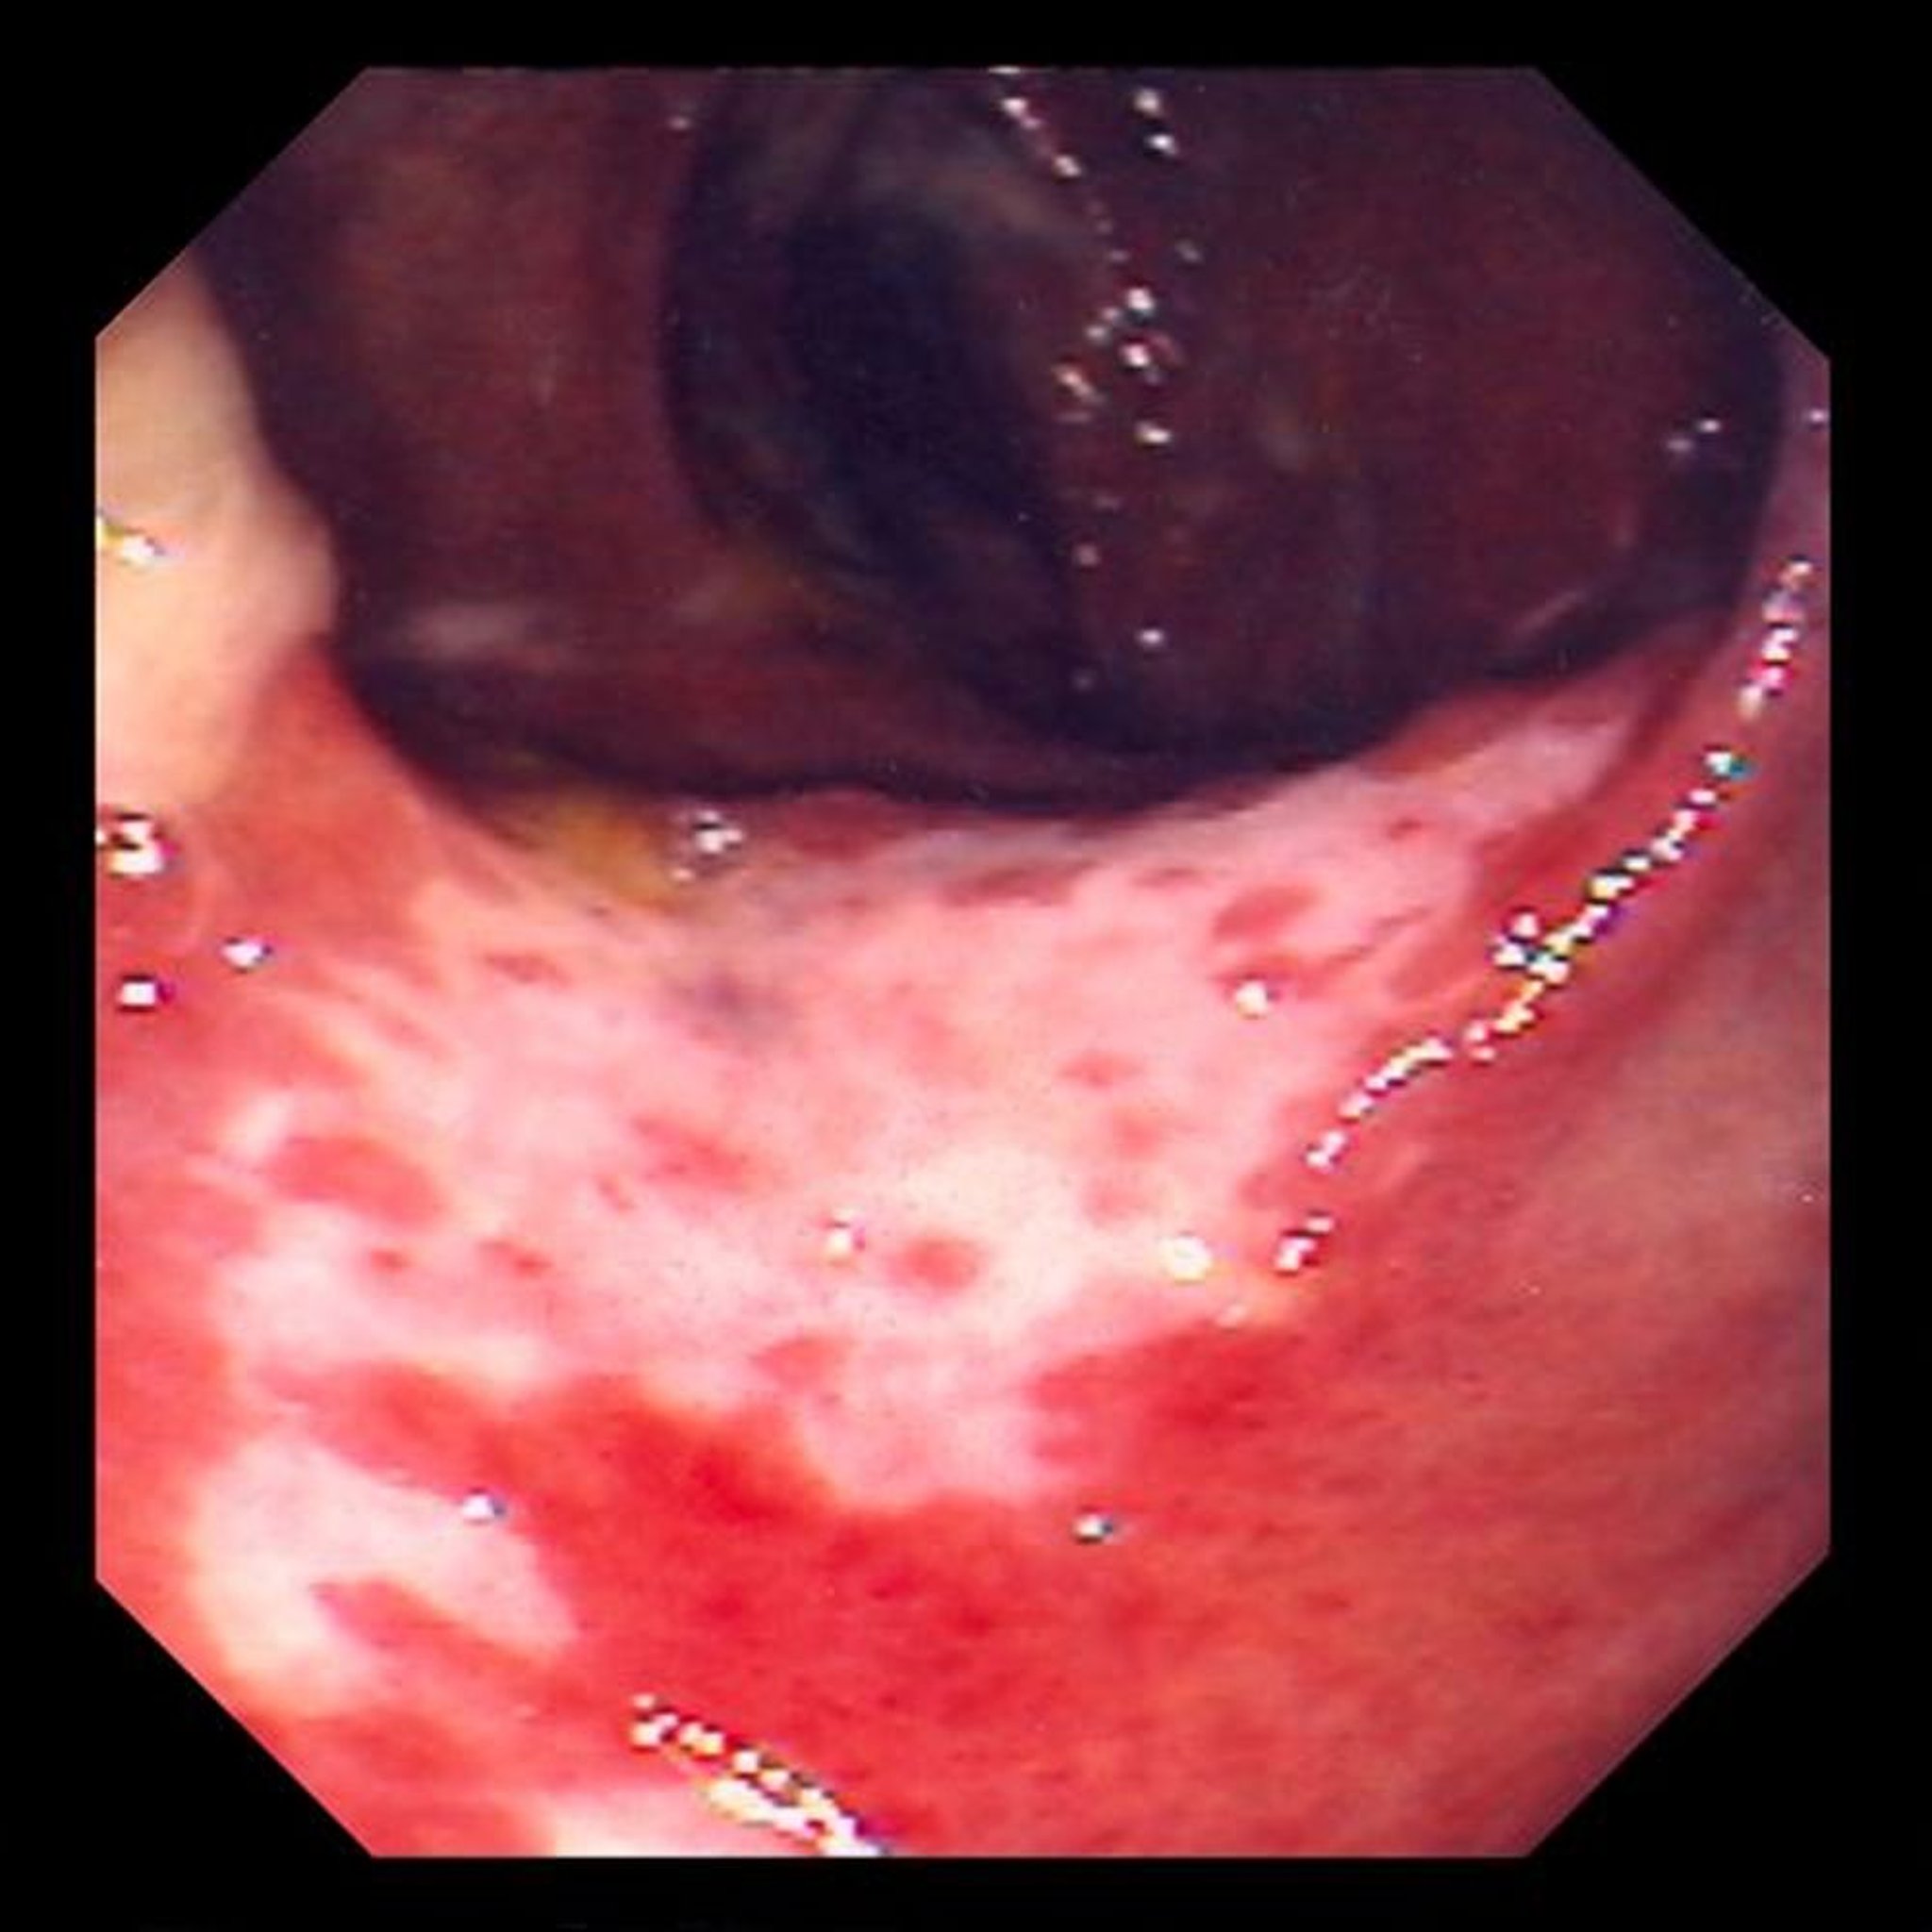

Colite ischémique (coloscopie)

Cette photo montre les dommages occasionnés à la muqueuse de l’intestin provoqués par le blocage de la circulation sanguine. La muqueuse de l’intestin est rouge et recouverte d’ulcères (zones blanches).

Photo fournie par le Dr David M. Martin.